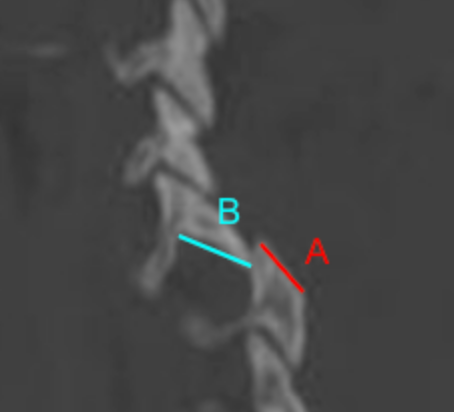

Image Type Cervical Spine X-Ray CT Scan MRI Scan Atlantodental Interval (ADI) Basion–Axial Interval (BAI) Basion–Dens Interval (BDI) Canal Occupying Ratio (COR) Clivo-Axial Angle Facet Joint Overlap (Percent Overlap Method) Facet Joint Step-Off/Dislocation Grabb-Oakes Measurement (pB - C2 line) Occipital Condyle–C1 Interval (CCI) Posterior Atlantodental Interval (PADI) Power’s Ratio Sagittal Vertical Axis (SVA) Segmental Angle Translation on Sagittal Reconstruction